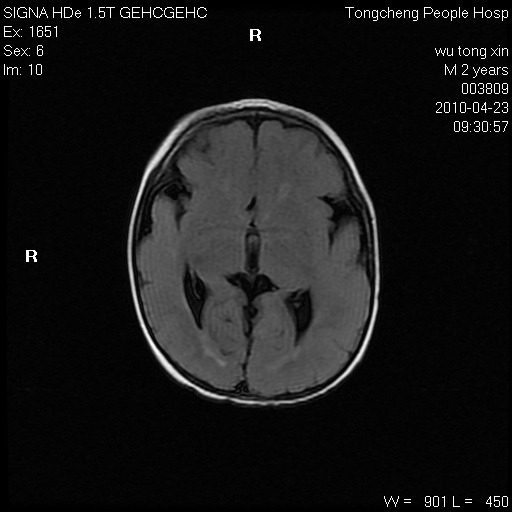

以下是引用赵物学在2010-4-25 12:43:00的发言:[br]巨脑回[br]侧脑室后角低密度影考虑hie或肾上腺脑白质营养不良?[br][br][本贴已被 赵物学 于 2010-4-25 12:51:28 修改过]

以下是引用gaoxiao在2010-4-25 16:54:00的发言:[br]巨脑回畸形。脑白质髓鞘化不良

以下是引用pujunzhi在2010-4-25 21:35:00的发言:[br]考虑 1双侧大脑皮质发育不良 2轻度脑积水 3双侧脑室后角旁片状长t1长t2信号,需继续观察,因为正常小儿此处脑白质的髓鞘化时间可以延迟到4-6岁,才显示正常。